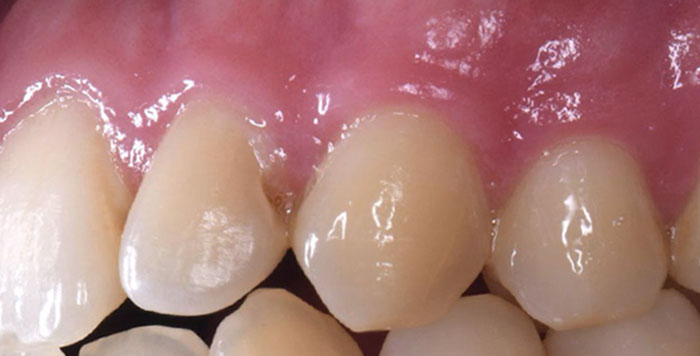

症例1:上の前歯の着色が気になる

治療前

治療後

治療中の様子

| 主訴 | 上の前歯の着色が気になる |

|---|---|

| 治療期間 | 1日 |

| 治療費 | ¥33,000×4歯(¥132,000) |

| 治療内容 | エナメル質形成不全や脱灰による着色を削らず、酸で溶かし、その後樹脂(レジン)を流し込んで修復しました。Resin infiltrationと言われている方法です。DMG社のIcon(アイコン)という製品を使用します。 削らずに着色部が改善しています。少し色が残っているところだけレジンで修復する予定でしたが、患者様が満足されたため、ひとまず終了となりました。 |

| 治療のリスク | 変色が完全に消えないことがあります。また、一時的に他の部分の色が白くなることがあります。 |